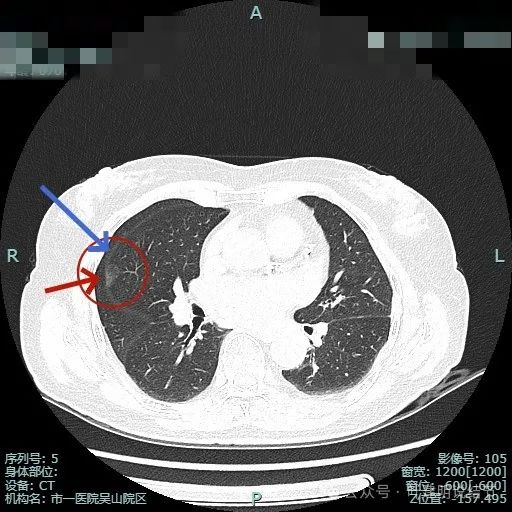

明明典型浸润性癌影像表现病理结果却是原位癌,原位癌也可表现为混合密度?

病史摘要:患者 3 个月前社区体检发现肺结节,就诊时医生考虑左上病灶基本为肺癌且倾向浸润性,因首次发现,建议口服抗炎 10 - 12 天,间隔 3 个月复查。此次复查无吸收好转及明显进展,拟手术治疗。诊疗过程:体格检查未提及。影像检查显示左上叶胸膜下混合密度结节,有血管弯征、胸膜牵拉等诸多恶性特征,下叶有次病灶。临床考虑左上叶病灶恶性且浸润性癌可能性大,建议手术。术中快速切片报腺癌

原位癌

典型

浏览 10 | 讨论 0